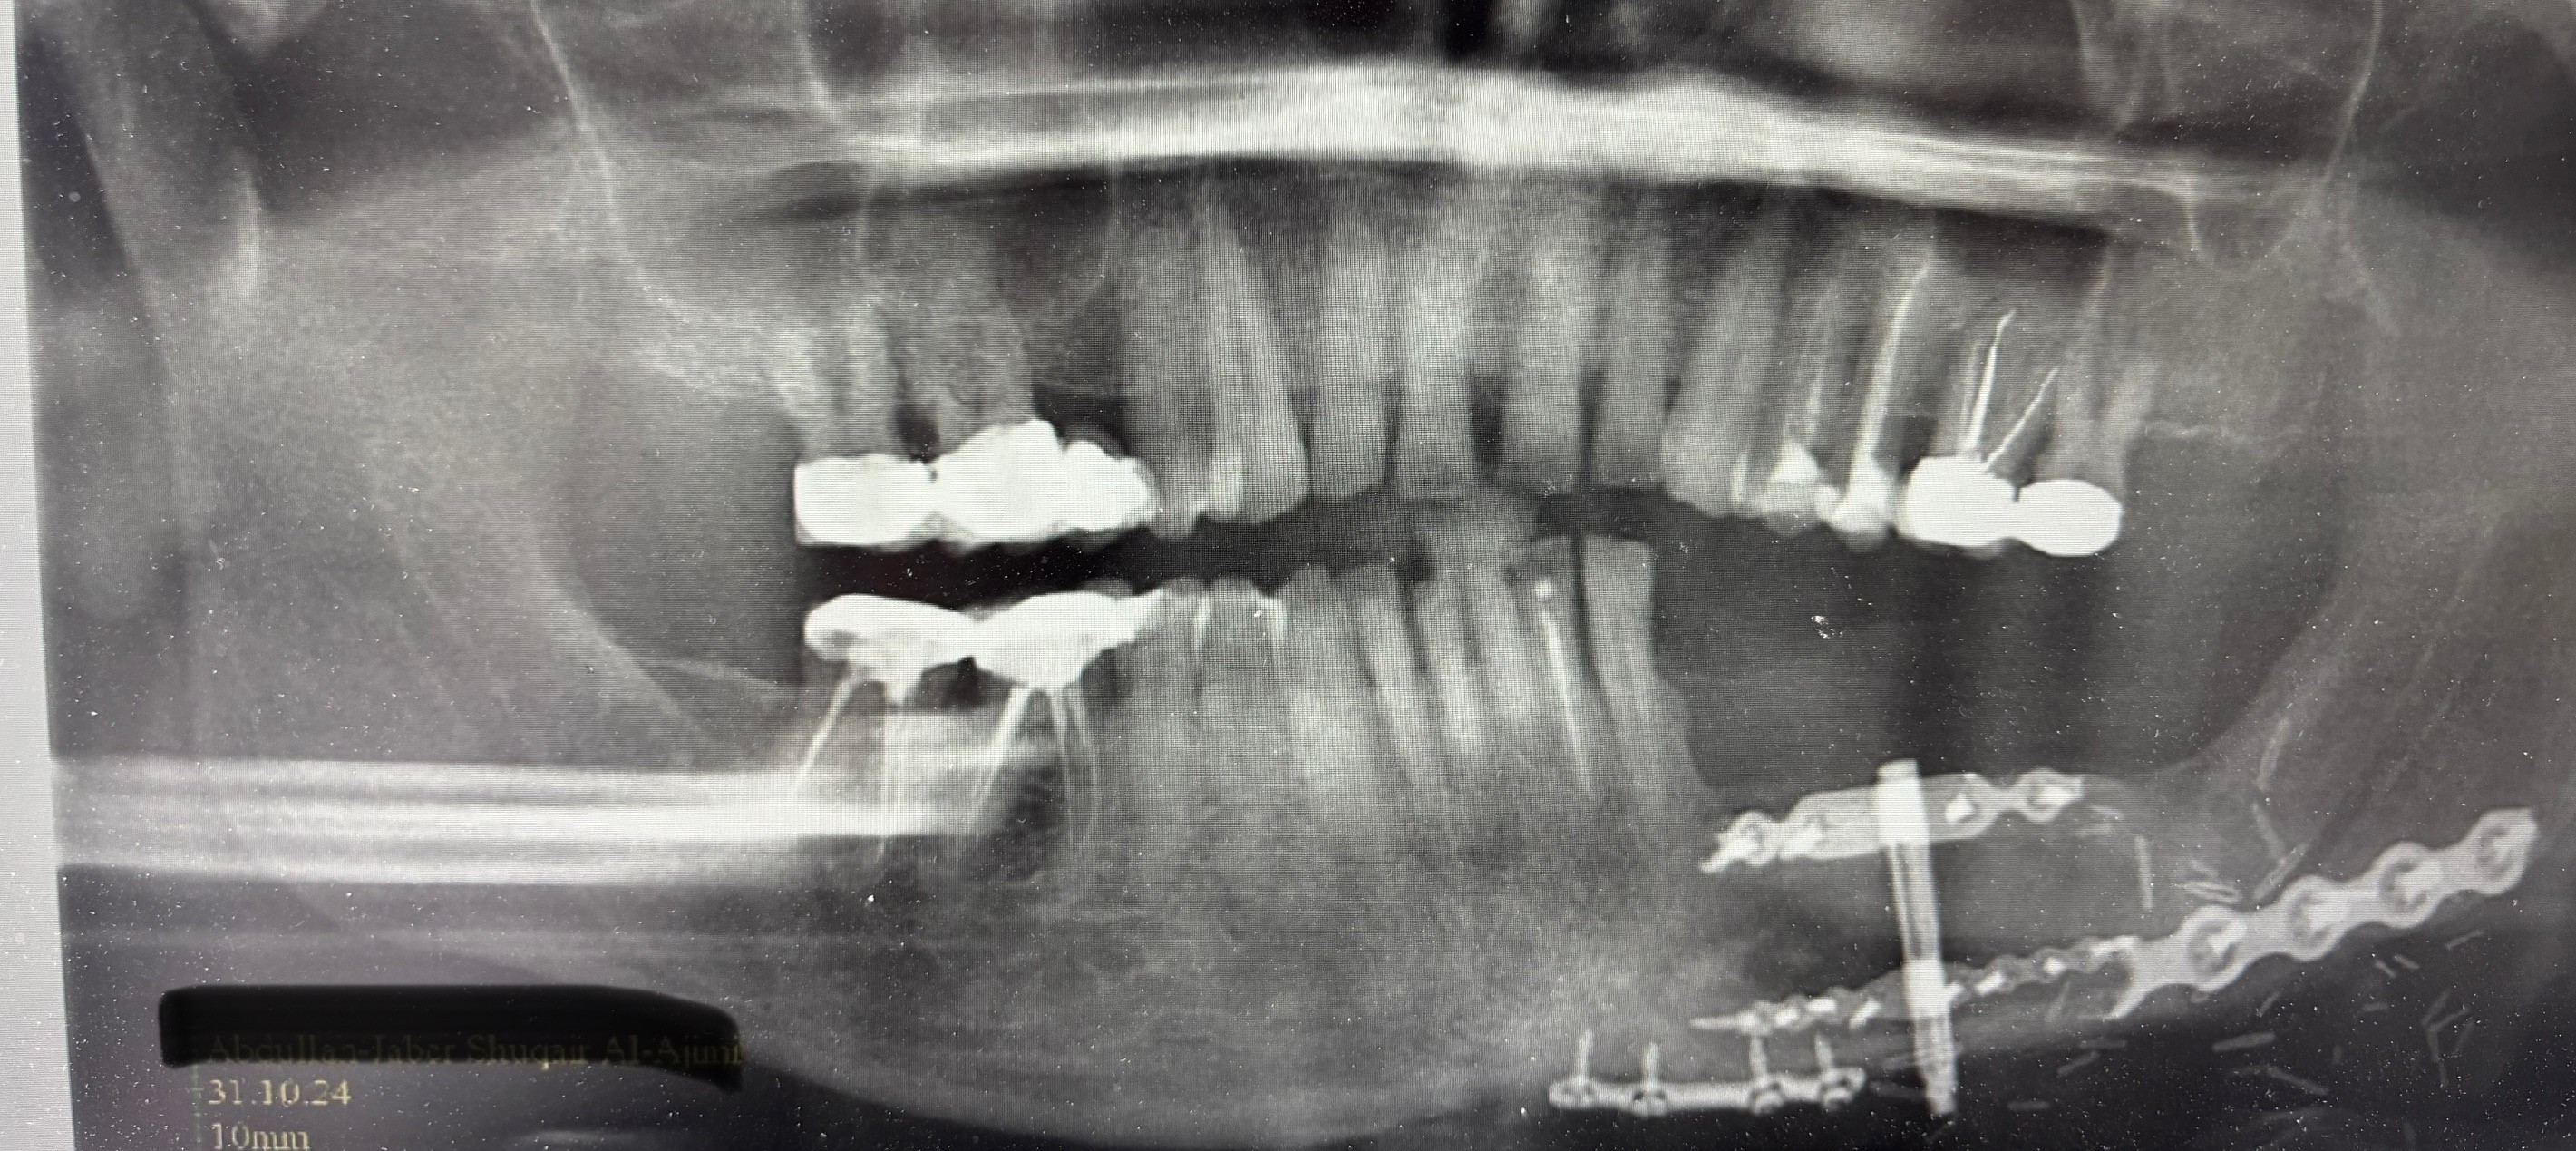

Insertion of distractor for placement of implants on a fibula flap post mandibula excision